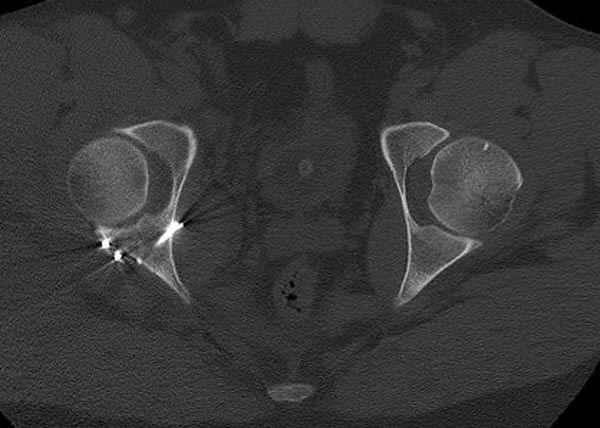

5:24 Рентгенограмма таза, вызывают врача ортопеда (снимок N1), его диагноз: закрытый переломо-вывих правого тазабедренного сустава, получает добро на закрытую репозицию в приемном отделении

N 2